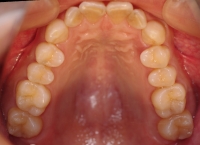

治療前 セファロ 治療前 上顎

治療後 セファロ 治療後 上顎

治療前 上顎

治療後 上顎